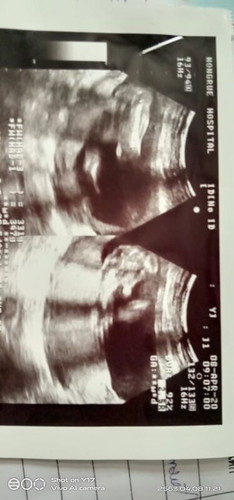

ภาพนี้ตั้งแต่18+3weekแล้วจ้าแม่ๆว่า หญิงหรือชาย คะ ตอนนี้36+1แล้วซาวอีกรอบลุงหมอไม่ได้บอกเพศเลย

ไม่ชัด แต่เดาจากภาพว่าชายค่ะ